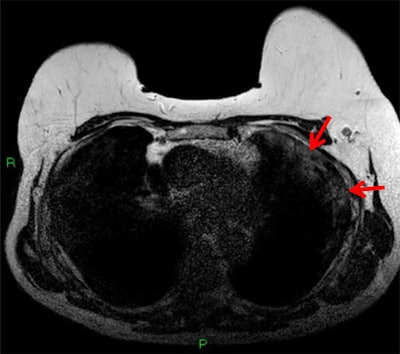

The woman was diagnosed with invasive lobular breast carcinoma after an abnormal mammogram result. She had been referred to the Royal Free Hospital radiology department for local staging, which showed unifocal carcinoma in the patient's upper, outer quadrant of her left breast.

But the breast cancer wasn't the patient's only notable MRI finding. The reading radiologist also spotted incidental findings in the pulmonary space on the patient's MRI, including abnormal subpleural high T2 signal intensity in the lung periphery and enhancement in subpleural regions on postcontrast, fat-saturated T1-weighted images.